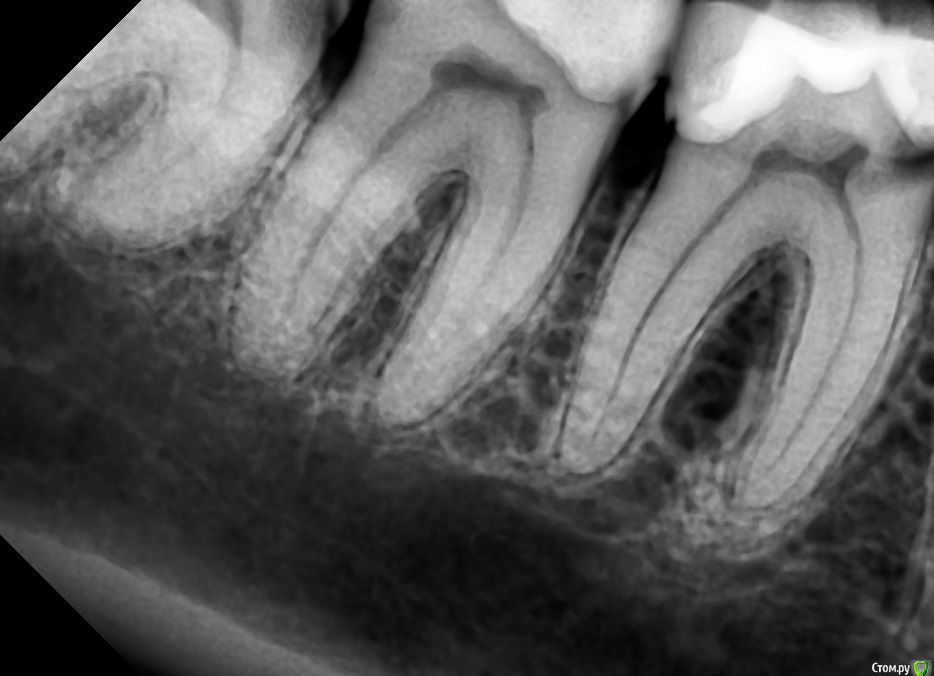

St. Опубликовано 3 февраля, 2016 Поделиться Опубликовано 3 февраля, 2016 Коронки на живые зубы в прогнозе действительно лучше, но по Вашему снимку кариес достаточно глубокий и есть довольно высокая вероятности хронического пульпита в 6 зубе. Я бы первоначально убрала весь кариес и заменила пломбы или восстановила и временные коронки. И понаблюдать пару недель. Если в процессе вскроется "нерв" или разболится - тогда конечно депульпировать.Р.С. Меня как-то очень смущает методика Обтачивать собирается за несколько раз понемногу, чтобы "не перегревать нерв" за 4-6 раз. . 3 Ссылка на комментарий

horoshie.veshi Опубликовано 4 февраля, 2016 Автор Поделиться Опубликовано 4 февраля, 2016 (изменено) Вам уже предложили вариант, начинайте с лечения. Так этим и занимаюсь. Сегодня вычистили полностью 8 (абсолютно спокоен) и 7 со стороны их контакта. Попросила еще снимки переделать до начала лечения, чтобы не было половины "отрезанных" зубов... http://s015.radikal.ru/i332/1602/7e/ff3dd3436447.jpg http://s019.radikal.ru/i640/1602/e1/69b726316ccd.jpg 7 с его небольшой полостью со стороны контакта в принципе, до пульпы-то далеко, но в процессе к концу третьего часа начал ощутимо колоть на бормашину и воздух + десна раскровилась, и вот сейчас поднывает, но терпимо... Даже, если допустить, что эти ощущения от "растревоженности" через несколько дней уйдут, не уверена я что-то в своем желании проходить его обточку живым, чтобы не то, что 6 раз, а даже пару-тройку это терпеть... С другой стороны депульпирование и чистку каналов я тоже переношу очень болезненно, никогда еще не было так, чтобы не подпрыгивала в кресле от боли, "уколы" сильные и глубокие, их не снимает даже двойная доза Ультракаина... Трудный выбор. Депульпировать можно в субботу, когда будем делать 6 и 7 со стороны контакта... Изменено 4 февраля, 2016 пользователем horoshie.veshi Ссылка на комментарий